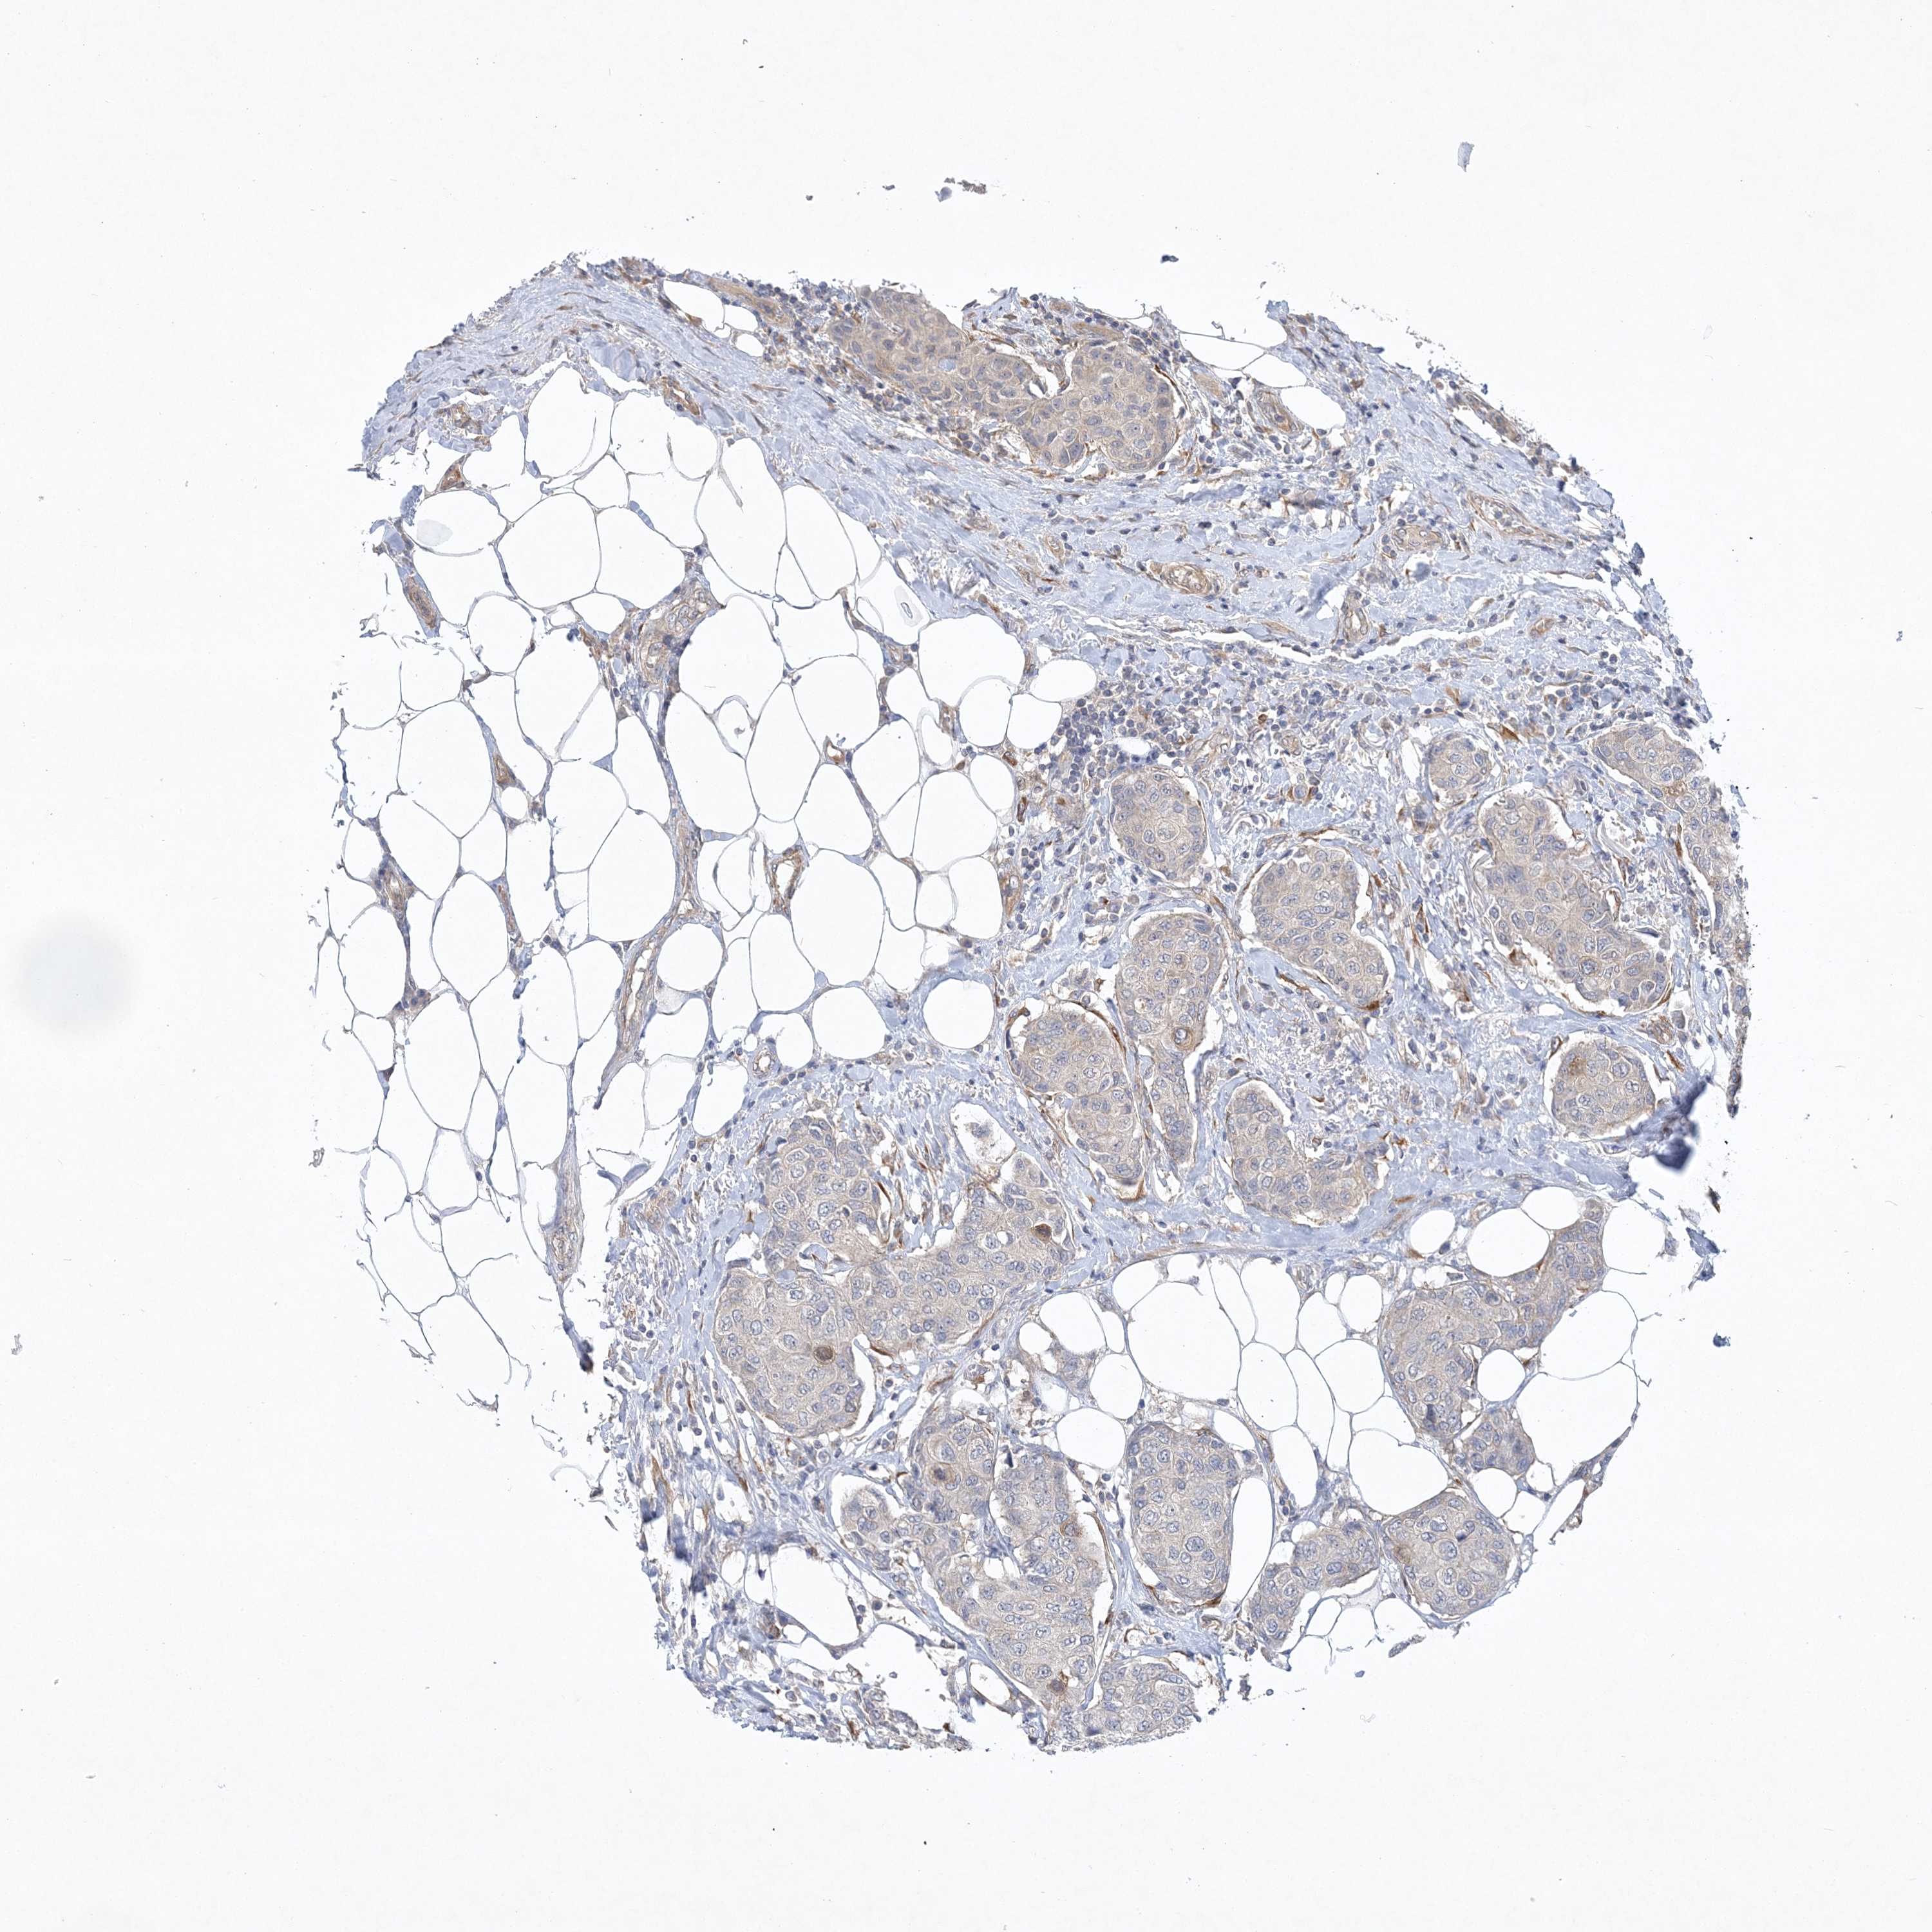

CANCER BREAST CANCER Show tissue menu

BRCA TCGA BRCA VALIDATION PROTEIN EXPRESSION

Breast cancer

Human cancer

Breast invasive carcinoma